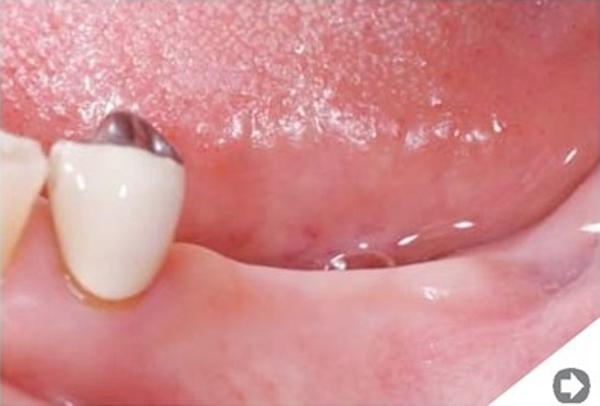

Przeszczep kości. W niektórych sytuacjach jest to jedyna skuteczna metoda odbudowy zanikłej kości. Zabieg polega na pobraniu fragmentu tkanki kostnej z innego miejsca jamy ustnej (albo przy większych przeszczepach z biodra) i następnym umocowaniu go w miejscu odbudowywanym. W ciągu kilku miesięcy następuje wgojenie się przeszczepu -€“ zamienia się on w pełnowartościową kość.